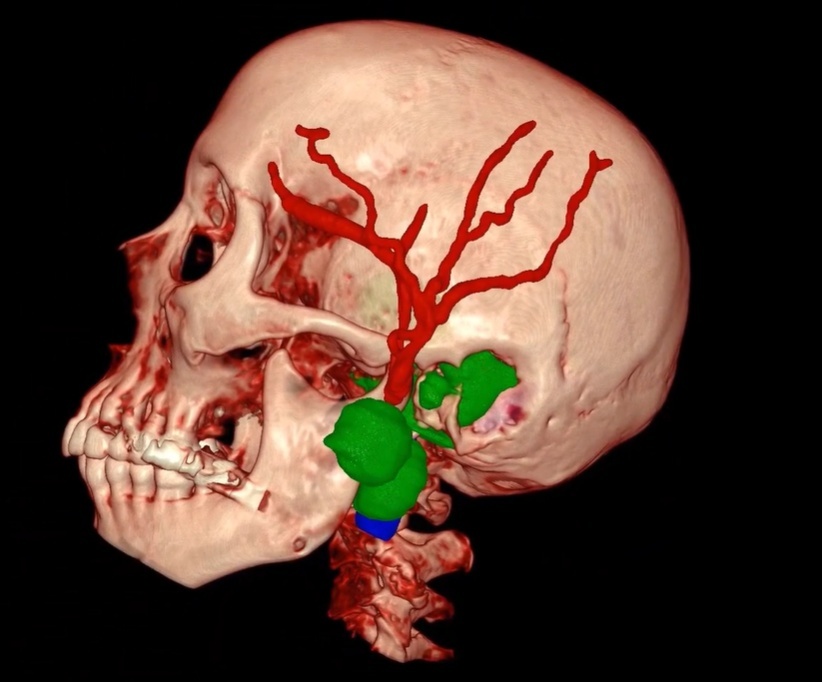

Now, imagine walking into this same house and immediately turning the lights on. Suddenly, everything is clear, and you can see each object and obstacle in the room. This is like seeing your anatomy in three dimensions. Now envision this same scenario as a doctor performing surgery. No two brains are alike, and working with a full 3D rendering means the house lights are on bright.

Enter the world of 3D surgery—a revolution that promises to bring the same richness and depth of our three-dimensional world into the operating room. With 3D imaging and surgical techniques, surgeons are no longer confined to flat representations. They can see the human body in its true form, with all its intricacies and details. This not only enhances their understanding but also empowers them and their patients to make more informed, precise decisions.

But the advancements don’t stop there. Surgeons are not only using these premier, patient-specific images in the clinic and for surgical planning but are also bringing them into the operating room for enhanced intraoperative visualization. This real-time, immersive detail allows surgeons to navigate complex procedures with unparalleled accuracy and confidence. At Surgical Theater, our mission is to deliver your 3D world throughout the patient’s entire continuum of care—from the patient’s consultation and surgical planning to the procedure itself. Imagine your surgeon practicing your surgery with this colorful rendering before entering the OR, transcending visual limitations and achieving a level of preparedness and precision that was previously unimaginable.